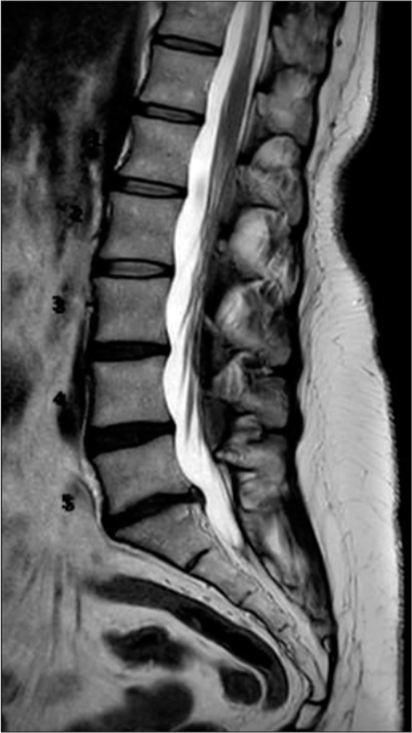

The images below are from just three of the many published case studies showing severe bulging discs in the neck and lower back that the nervous system was able to heal naturally:

Case Study 1: